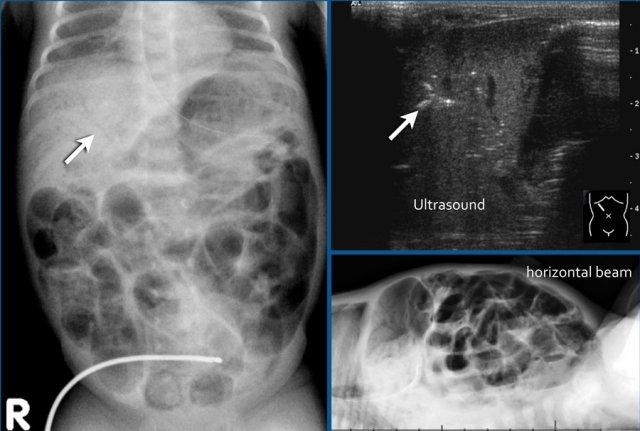

Tràn khí ổ bụng trong viêm ruột hoại tử nặng.

Khí có thể được nhìn thấy ở cả hai phía của thành ruột.

Đây được gọi là dấu hiệu Rigler.

Hình ảnh bên trái được chụp 6 ngày sau sinh, cho thấy ruột giãn với khí trong thành ruột.

Hình chụp thụt tháo đại tràng lúc 6 tuần tuổi cho thấy hẹp ở đại tràng xuống (mũi tên).